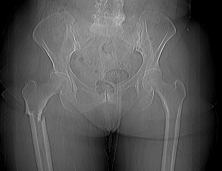

王阿姨(化姓),女,73歲。自述2個月前無明顯誘因出現(xiàn)右大腿疼痛,當時未予治療。就診前1小時,她在活動后出現(xiàn)右大腿疼痛加重,同時伴局部畸形、異;顒,隨即前往醫(yī)院就診。急診行X線檢查后,被診斷為右股骨近端骨折。

骨盆正位片

經(jīng)進一步了解,得知老人6年前曾因摔傷致“右橈骨遠端骨折”進行手術治療,住院期間確診為重度骨質疏松,出院后一直應用雙膦酸鹽藥物抗骨質疏松。本次輕微活動后即出現(xiàn)骨折,住院后通過綜合病史、查體、檢查、檢驗等綜合評估,診斷為長期應用雙膦酸鹽類藥物出現(xiàn)的一種特殊類型骨折:非典型骨折(股骨),患者隨后進行手術治療。